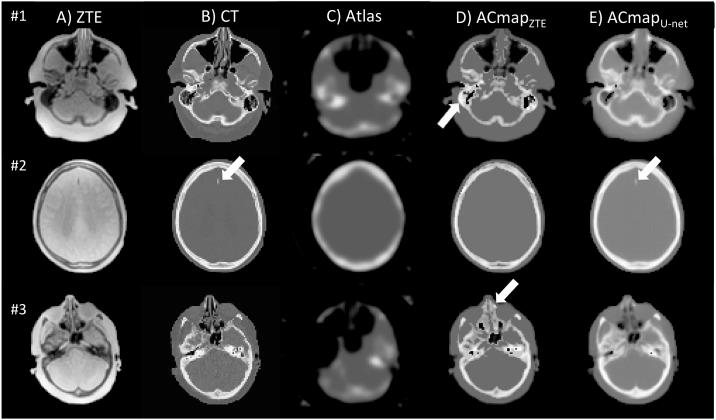

One of the main technical challenges of PET/MRI is to achieve an accurate PET attenuation correction (AC) estimation. In current systems, AC is accomplished by generating an MRI-based surrogate computed tomography (CT) from which AC-maps are derived. Nevertheless, all techniques currently implemented in clinical routine suffer from bias. We present here a convolutional neural network (CNN) that generated AC-maps from Zero Echo Time (ZTE) MR images. Seventy patients referred to our institution for 18FDG-PET/MR exam (SIGNA PET/MR, GE Healthcare) as part of the investigation of suspected dementia, were included. 23 patients were added to the training set of the manufacturer and 47 were used for validation. Brain computed tomography (CT) scan, two-point LAVA-flex MRI (for atlas-based AC) and ZTE-MRI were available in all patients. Three AC methods were evaluated and compared to CT-based AC (CTAC): one based on a single head-atlas, one based on ZTE-segmentation and one CNN with a 3D U-net architecture to generate AC maps from ZTE MR images. Impact on brain metabolism was evaluated combining voxel and regions-of-interest based analyses with CTAC set as reference. The U-net AC method yielded the lowest bias, the lowest inter-individual and inter-regional variability compared to PET images reconstructed with ZTE and Atlas methods. The impact on brain metabolism was negligible with average errors of -0.2% in most cortical regions. These results suggest that the U-net AC is more reliable for correcting photon attenuation in brain FDG-PET/MR than atlas-AC and ZTE-AC methods.

正电子发射断层磁共振成像(PET/MRI)的主要技术挑战之一是实现准确的 PET 衰减校正(AC)估计。在当前的系统中,通过生成基于 MRI 的替代计算机断层扫描(CT)来完成 AC,从中得出 AC 图。然而,目前在临床常规中实施的所有技术都存在偏差。我们在这里提出了一种卷积神经网络(CNN),它可以从零回波时间(ZTE)MR 图像生成 AC 图。我们纳入了 70 名因疑似痴呆而在我院接受 18FDG-PET/MR 检查(SIGNA PET/MR,GE Healthcare)的患者。23 名患者被添加到制造商的训练集中,47 名患者用于验证。所有患者均提供脑部 CT 扫描、两点 LAVA-flex MRI(用于基于图谱的 AC)和 ZTE-MRI。我们评估并比较了三种 AC 方法与基于 CT 的 AC(CTAC):一种基于单个头部图谱,一种基于 ZTE 分割,一种基于 3D U-net 架构的 CNN,用于从 ZTE MR 图像生成 AC 图。结合基于体素和感兴趣区域的分析,将 CTAC 作为参考,评估对脑代谢的影响。与使用 ZTE 和图谱方法重建的 PET 图像相比,U-net AC 方法的偏差最小,个体间和区域间的变异性最小。对大脑代谢的影响可以忽略不计,大多数皮质区域的平均误差为-0.2%。这些结果表明,与图谱-AC 和 ZTE-AC 方法相比,U-net AC 更可靠地校正脑 FDG-PET/MR 中的光子衰减。